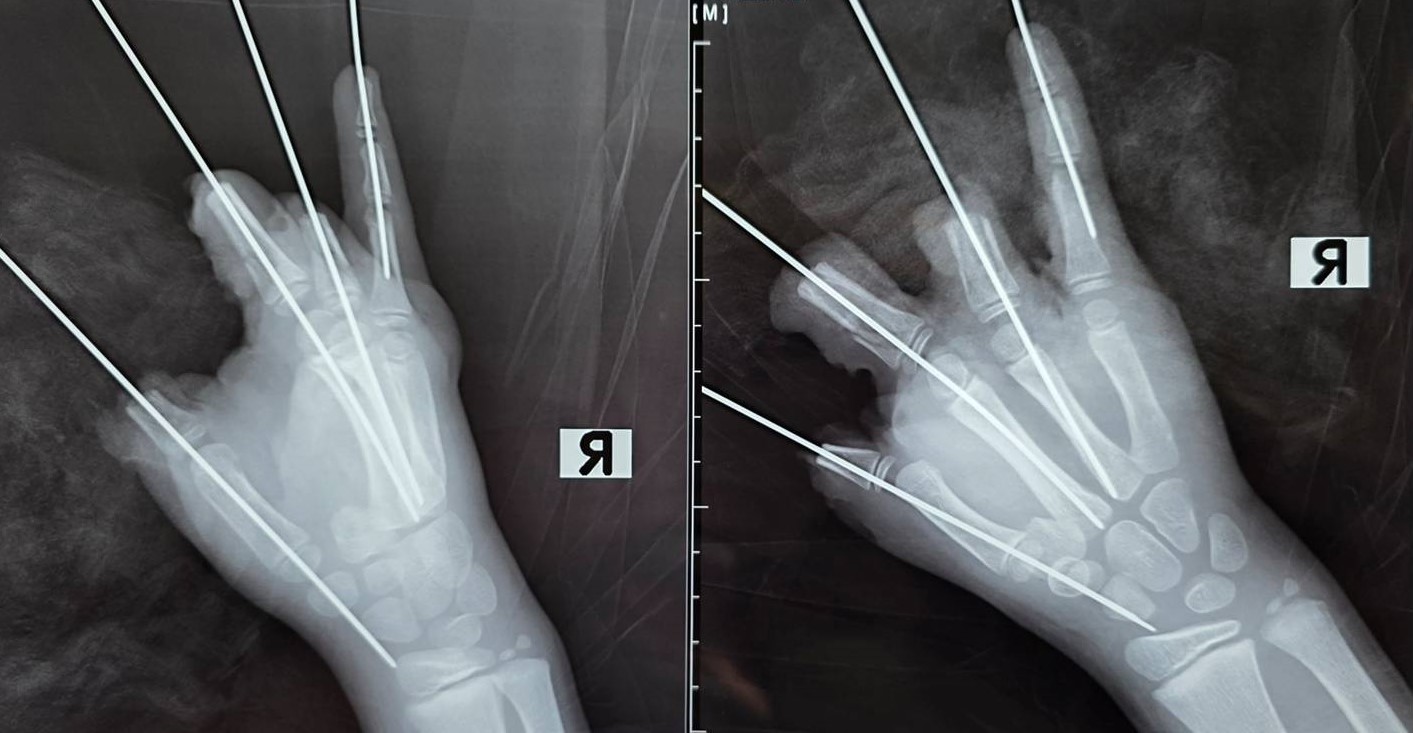

В результате взрыва школьнику оторвало четыре пальца на правой руке, с большого по безымянный. Мизинец уцелел, хотя был сильно поврежден. Кроме того, врачи диагностировали у юного пациента открытый перелом и вывих пястной кости, размозжение и множественные дефекты мягких тканей кисти.

«Врачи выполнили удаление свободно лежащих фрагментов костей, соединили отломки фаланг среднего и безымянного пальцев посредством металлоостеосинтеза. Также специалисты провели щадящую первичную хирургическую обработку с удалением явно нежизнеспособных тканей и сформировали культи большого, среднего и безымянного пальцев на уровне проксимальных фаланг», - описала хирургические манипуляции пресс-служба СПбГПМУ.